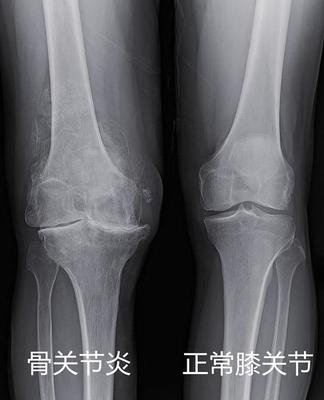

一张膝关节X光片,是膝关节炎的标准检查,也是最简单,最便宜,最有价值的。

关节间隙很狭窄了 这种一般需要换关节了

如果x光片报告上告诉你,“退行性改变”、“骨赘形成”、“间隙变窄”、“髁间嵴变尖”、“软骨下骨硬化/囊变”,这些都是关节炎患者,常常出现的。

如果核磁共振报告上告诉你,“软骨厚度变薄/缺损”“骨髓水肿”“少量关节积液”“腘窝囊肿”“软骨下骨囊性变”甚至是“半月板退变/变性/损伤”,这些也都常常是不同程度关节炎患者的提示。当然,如果你近期有膝盖受伤后症状加重,或者你是年轻人,出现半月板损伤等,就要另加重视了。